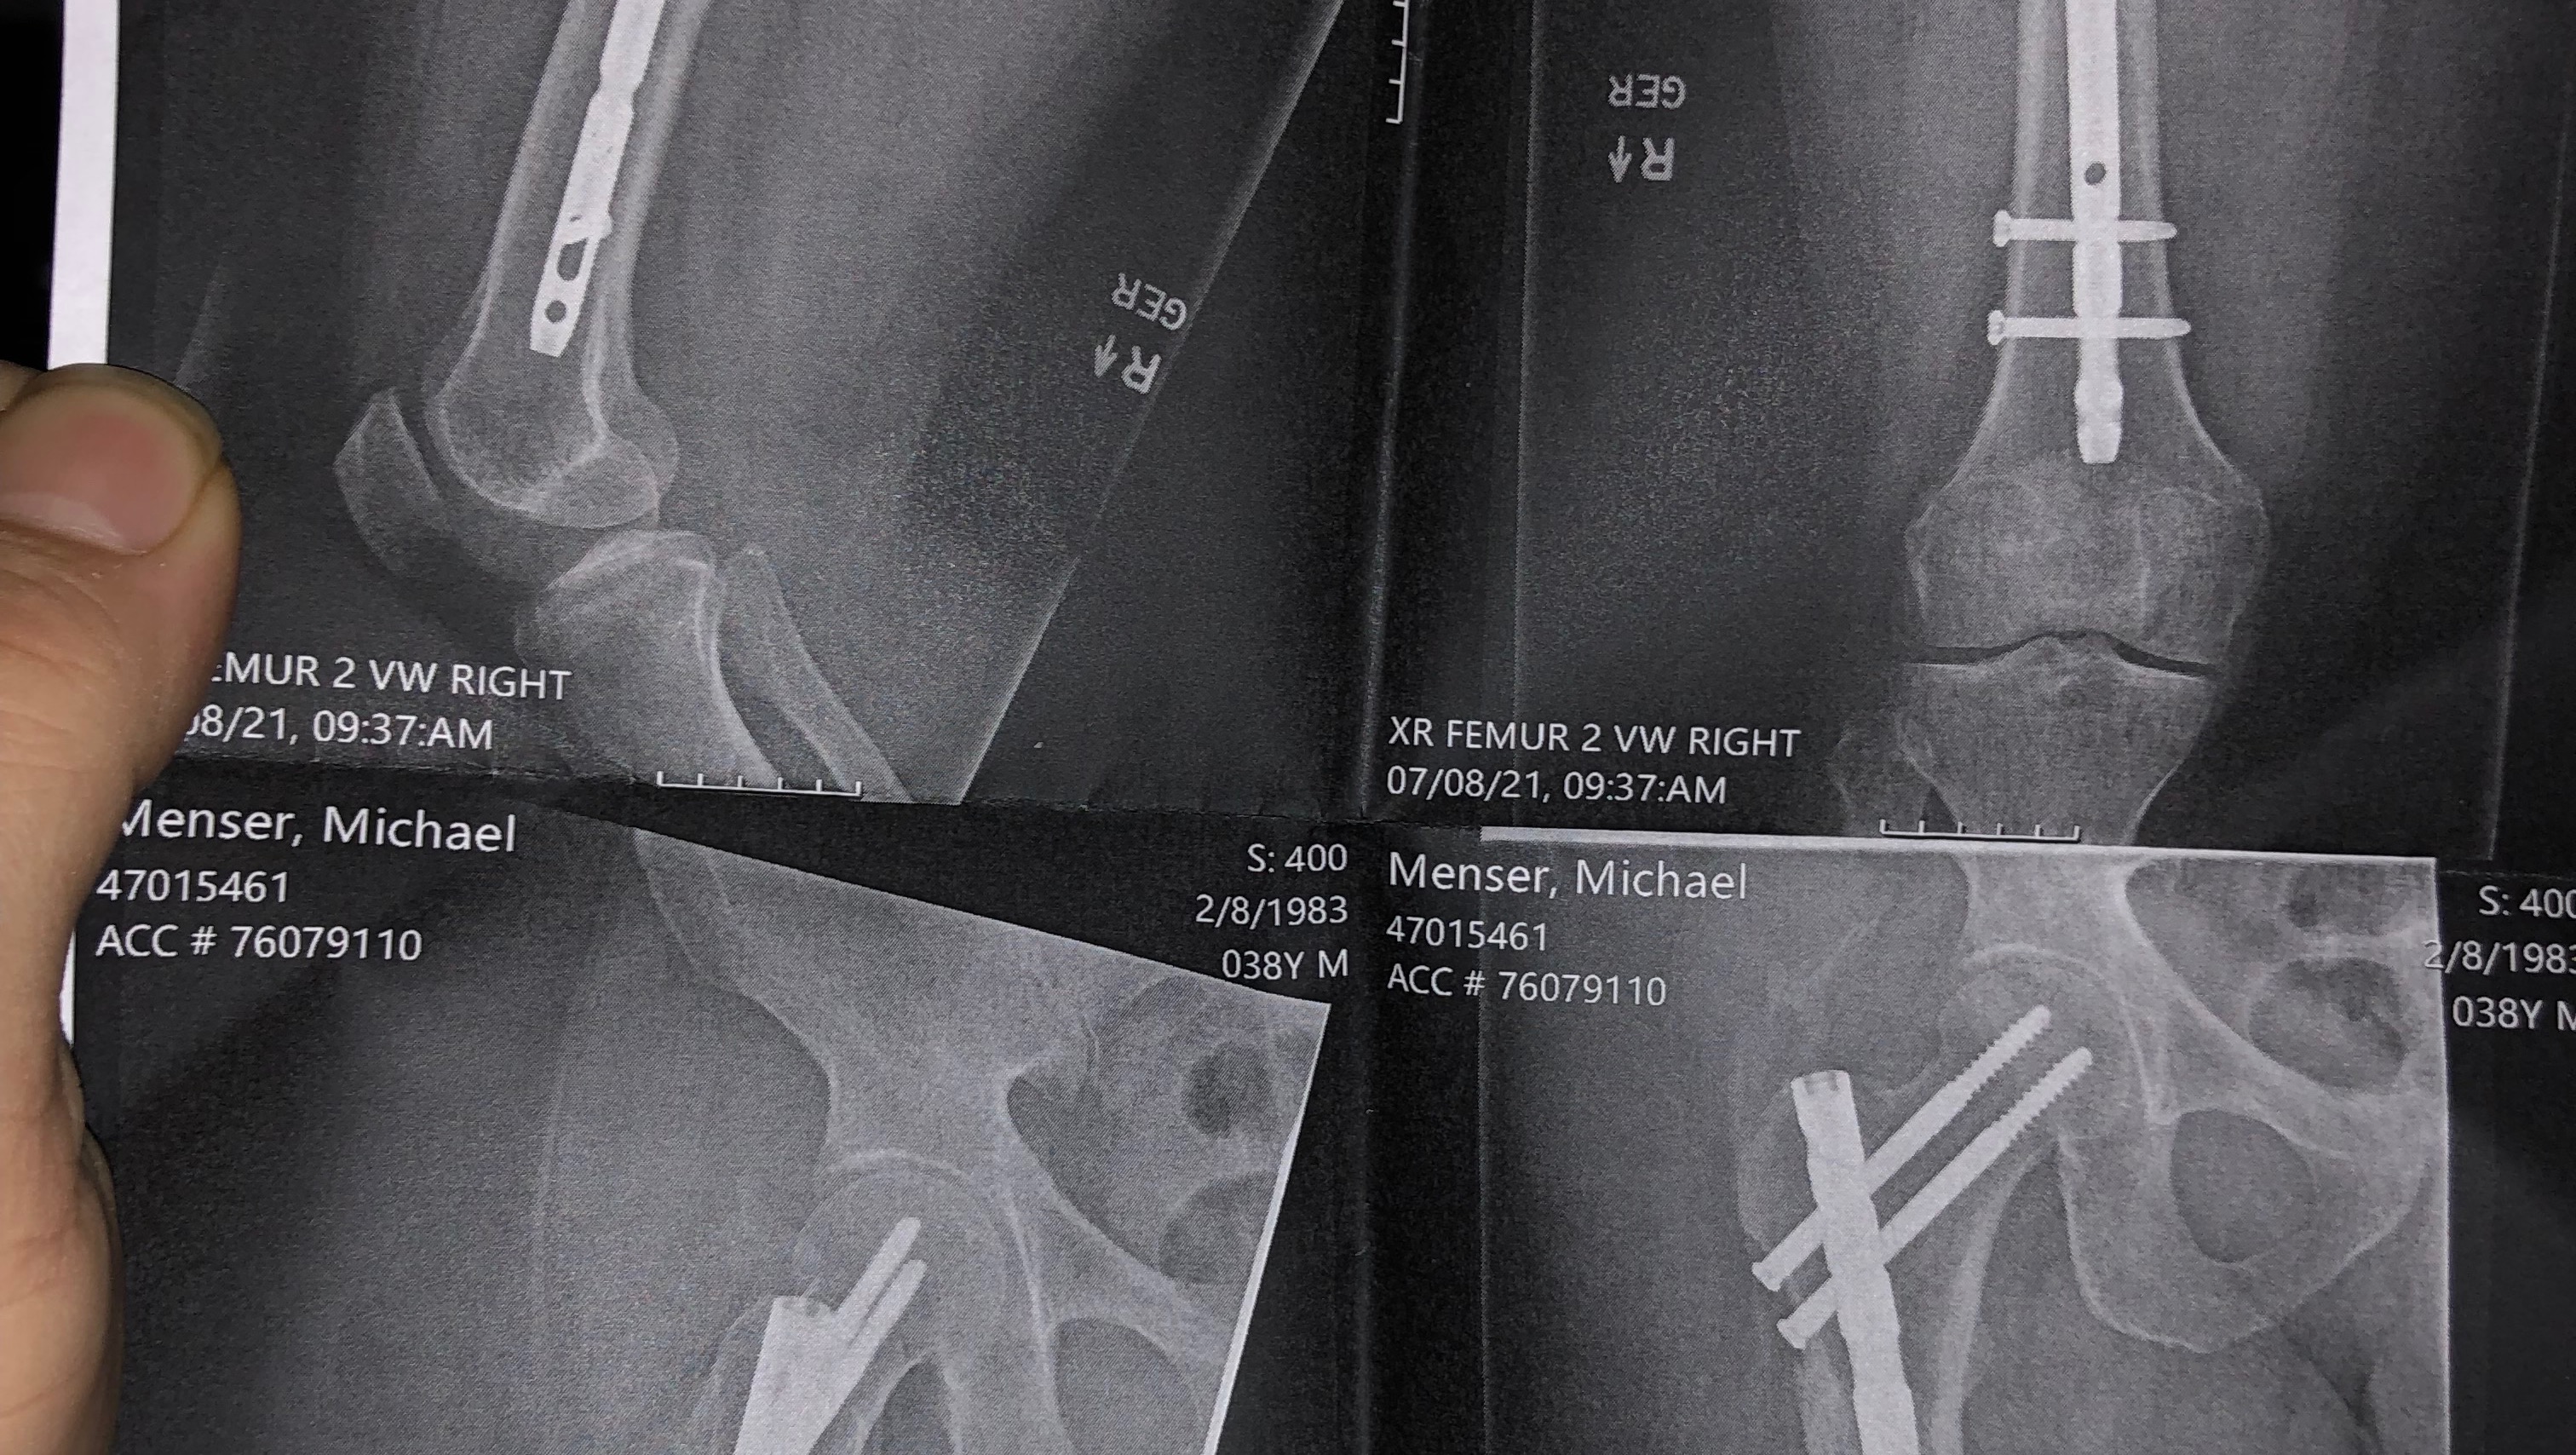

Please, anyone, I need help. We are about to lose our home!!! We don’t want to lose our home, our pets, our dogs, our cats, or everything inside our home. I had a very bad, God-awful wreck at the end of 2020 that left me unable to do just about anything, let alone be able to work to provide for my family. My wife had to take on the role of working, but it is not enough for the mortgage and utilities, and we’ve gone through all of our funds to stay above water.